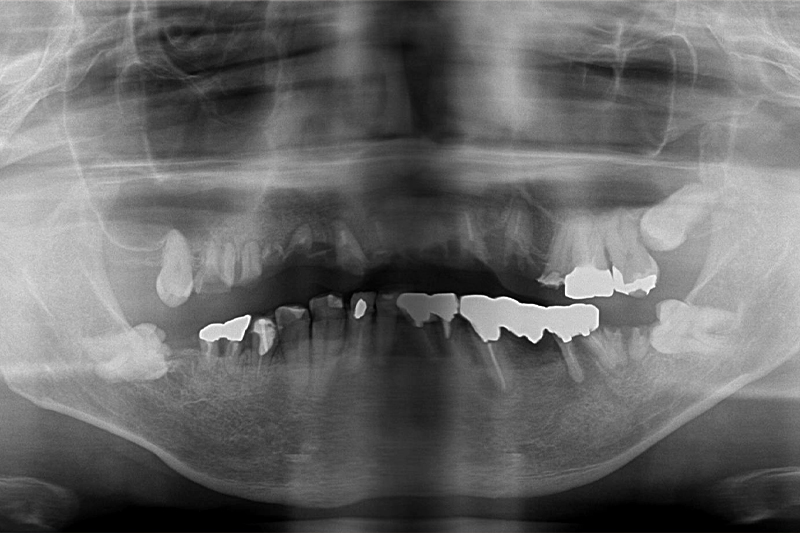

レントゲン写真の比較

-

治療前のレントゲン写真

治療後のレントゲン写真

| 主訴 | 被せものがとれたり、抜けたりした所を直したい。 |

|---|---|

| 治療期間 | 1年8か月 |

| 治療費 | 上顎3,465,000円(税込)・ 下顎1,430,000円(税込) |

| 治療内容 | 上顎 インプラントフィクスチャー6本・ 上部構造11歯・サイナスリフト 下顎 インプラントフィクスチャー3本・ 上部構造4歯 |

| 治療のリスク | ・インプラント手術後は反応性の出血、腫れ、あざがでる場合があります。 ・喫煙、糖尿病、加齢、清掃不良などに伴いインプラント周囲の骨に炎症が起こり、再治療が必要になる場合があります。 ・治療後5年以内であれば無償で再治療を行います。5年の完全保証を受けるには当院にて年1~2回以上のインプラントメンテナンスが必要になります。 ・それ以降は永久的に20%の部分的保証期間となります。 こちらも、年1~2回以上のインプラントメンテナンスを受けていることが必要になります。 |